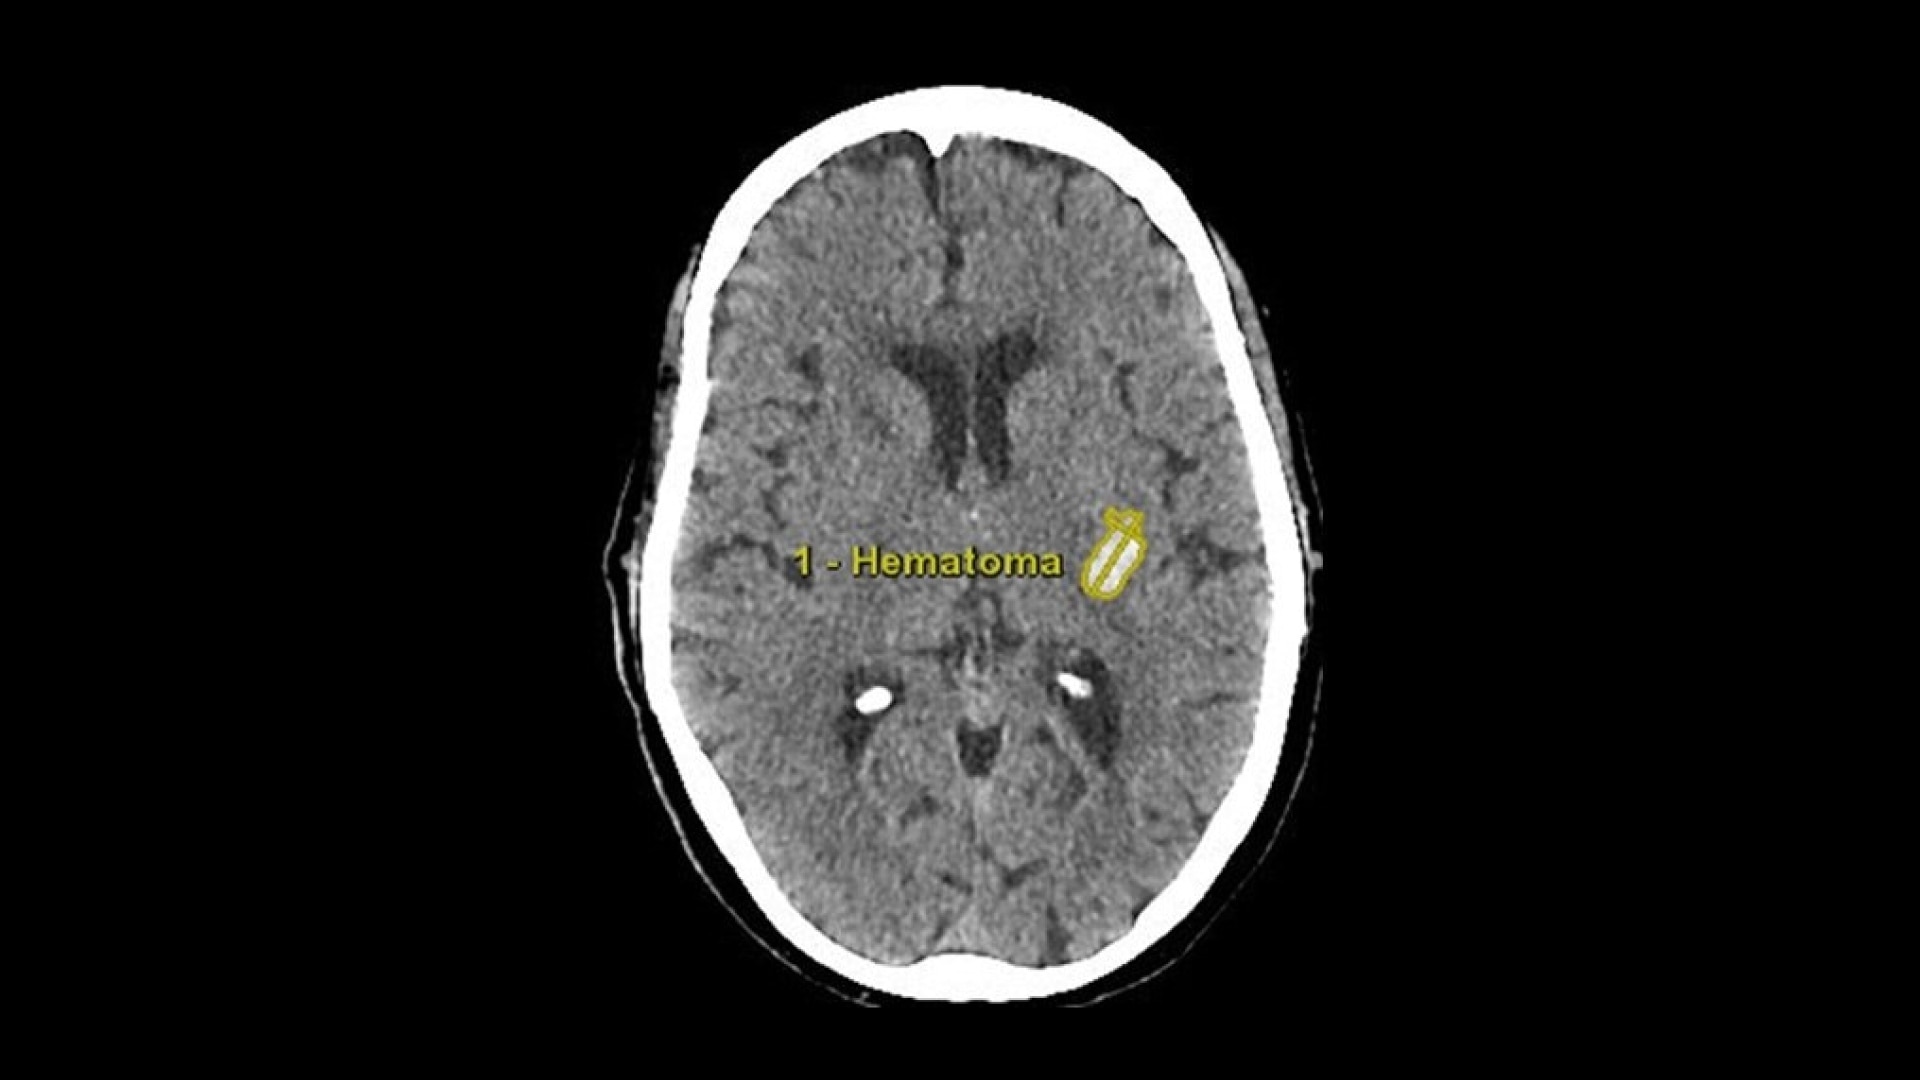

Hematoma

Semi-automated segmentation and sizing of hematoma.

• Semi-automated segmentation and sizing of hematoma

• Track hematoma changes both visually and quantitatively with longitudinal exam workflow